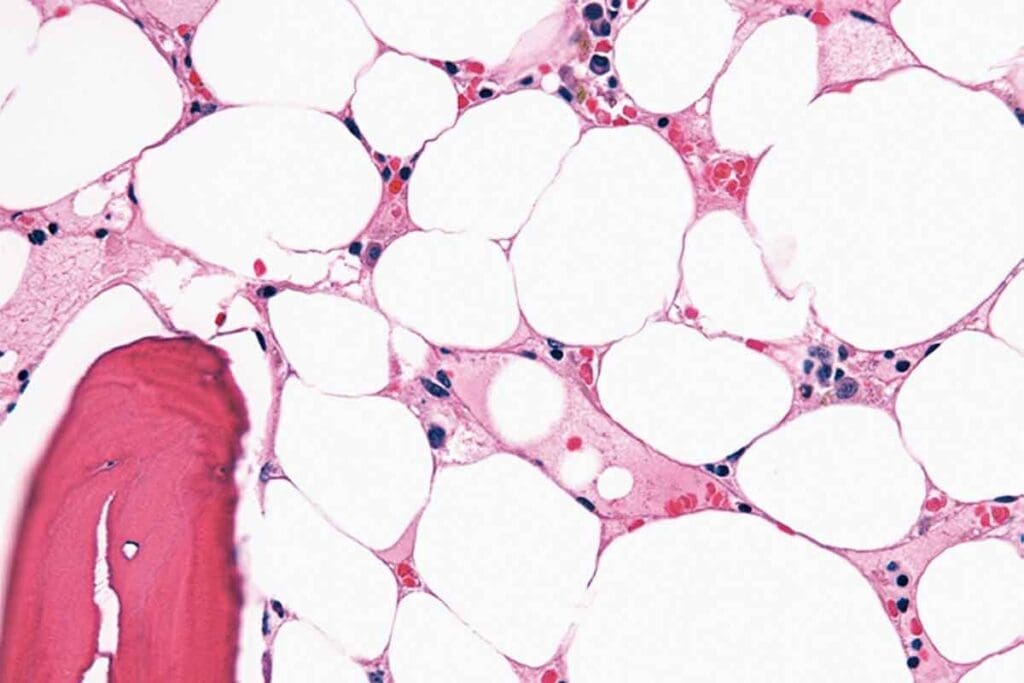

Bone Marrow Failure in Aplastic Anemia

In aplastic anemia, the bone marrow can’t make enough blood cells. This happens when the bone marrow gets damaged. It leads to fewer red blood cells, white blood cells, and platelets.

Bone Marrow Biopsy and Aspiration

A bone marrow biopsy and aspiration are vital for confirming aplastic anemia. These procedures remove a bone marrow sample for examination. In aplastic anemia, the bone marrow has fewer cells than normal.

The biopsy helps assess the marrow’s health and look for abnormalities like fibrosis or cancer cells.